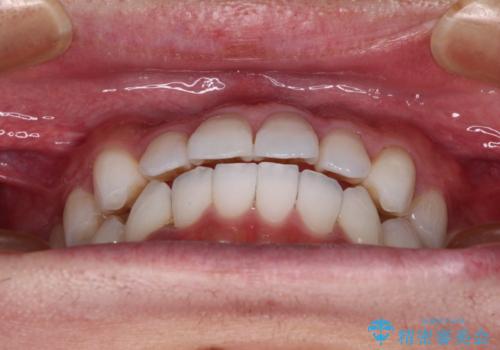

今回は、ワイヤー装置を併用することなく治療を行い、トラブルなく、満足のいく歯列に整えることができました。

矯正治療の途中でホームホワイトニングを併用され、術前とは見違えるほどきれいな口元となりました。